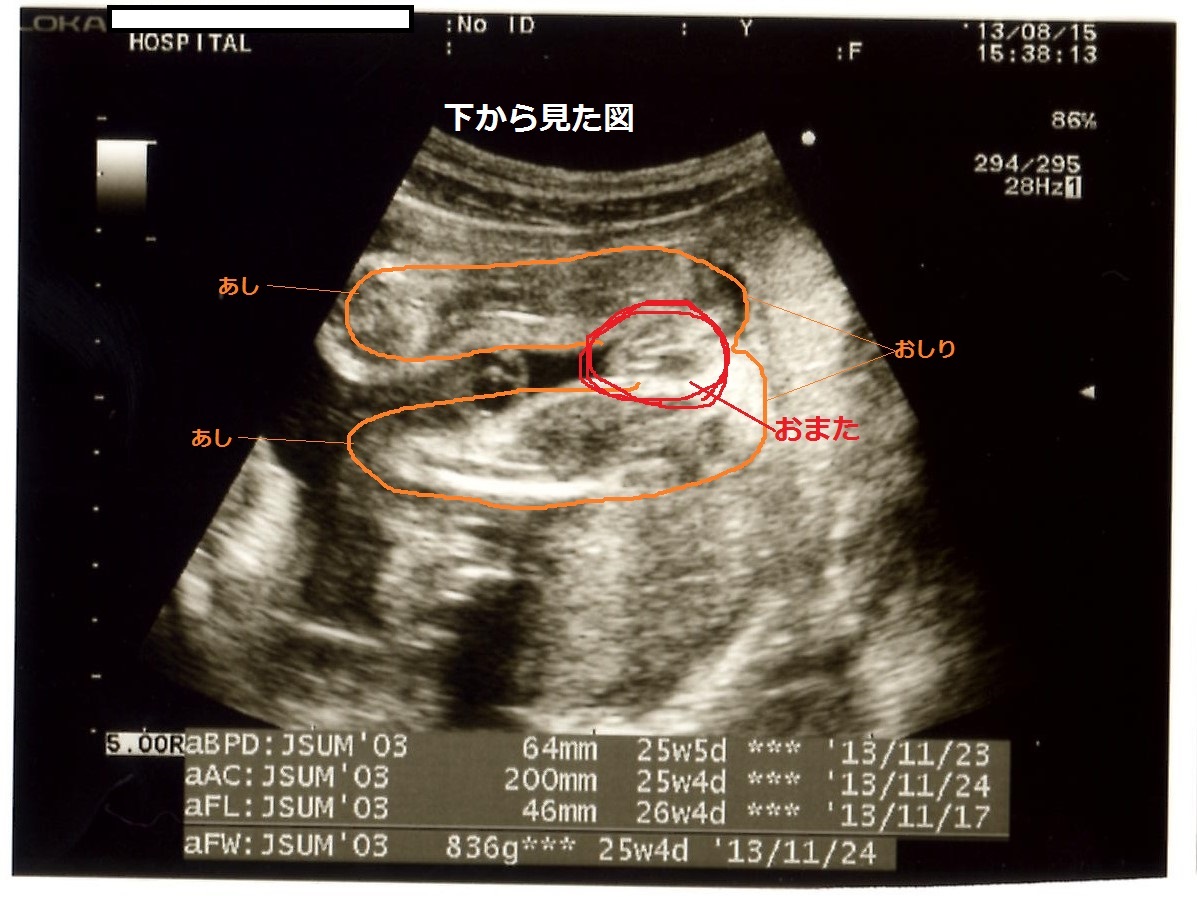

エコー 女の子 木の葉. 妊娠 - エコーでみる赤ちゃんの性別(山が二つで女の子?) 妊娠34週に入りました。 先日までまだ性別が確定していなかったのですが、 エコーの結果、先生に女の子だと言われました。 股の下からの画像では... 女の子の証拠エコー「木の葉形」を 41歳5人目にして 初めて知ったjunなのでした☆ でも思い出してみると 先月に男の子って言われて 「妊娠7ヶ月 エコー 男の子 間違い」 とかいろいろググって見てる時に 「木の葉」ってキーワードは見た気がする!. 妊娠24週ってどんな時期?! エコーで赤ちゃんの性別が確定できました♡女の子の場合でも断定できる!葉っぱマークや子宮が見えるって本当?? そしてツワリも終わって気をつけたいのが体重管理!! 妊娠中の体重増加の目安って?ツワリで減った場合は、どの時点の体重から考えるべき?.

ゴールデンウィーク イラスト-ゴールデンウィーク イ ;. エコーで木の葉型だったら女の子? 妊娠中 コメントの数:4 ハートの数:0 エコーで突起物やピーナッツ型のようなものが見えたら男の子、股の間に木の葉のようなものが見えたら女の子って聞きませんか?. こちらの記事に対するkozokaeruさんのブックマークです → 「“胎児 エコー 女の子 割れ目女の子 エコー 木の葉 写真女の子 エコー 突起物 画像エコー写真 男の子 女の子 違い女の子 エコー 写真 突起物男の子エコー写真股女の子 エコー 写真 葉っぱ妊娠 性別 エコー 見分け方エコー 」.

赤ちゃんがお腹の中にいることが分かると、とても幸せな気持ちになますね。 妊娠が発覚して、まず何が気になるって…赤ちゃんの性別です!! うちのパパは女の子希望でしたので、ずっとエコー写真を見ては 「これは女の.. 女の子エコー写真股 — エコー検査で、赤ちゃんの性別が判明するのはいつごろなのでしょうか。写真の見分け方や男の子、女の子それぞれの見え方の特徴を画像付きで解説します。男の子はピーナツ状の突起物、女の子は木の葉やコーヒー豆が股間に見えますが、ときには判定間違いも起こり .. エコー写真から性別判定お願いします 妊娠28週です 担当の先生には男 こちらの記事に対するkozokaeruさんのコメントです 胎児 エコー 女の子 割れ目女の子 エコー 木の葉 写真女の子 エコー 突起物 画像エコー写真 男の子 女の子 違..

女の子 の場合は、突起物はなく、 太ももの間に 木の葉のようなもの が見えます。 また、子宮と膀胱がふたつの黒い点として エコー写真に写ります。 ※女の子に恵まれれば、いつか写真参考アップしますね٩(•౪• ٩).